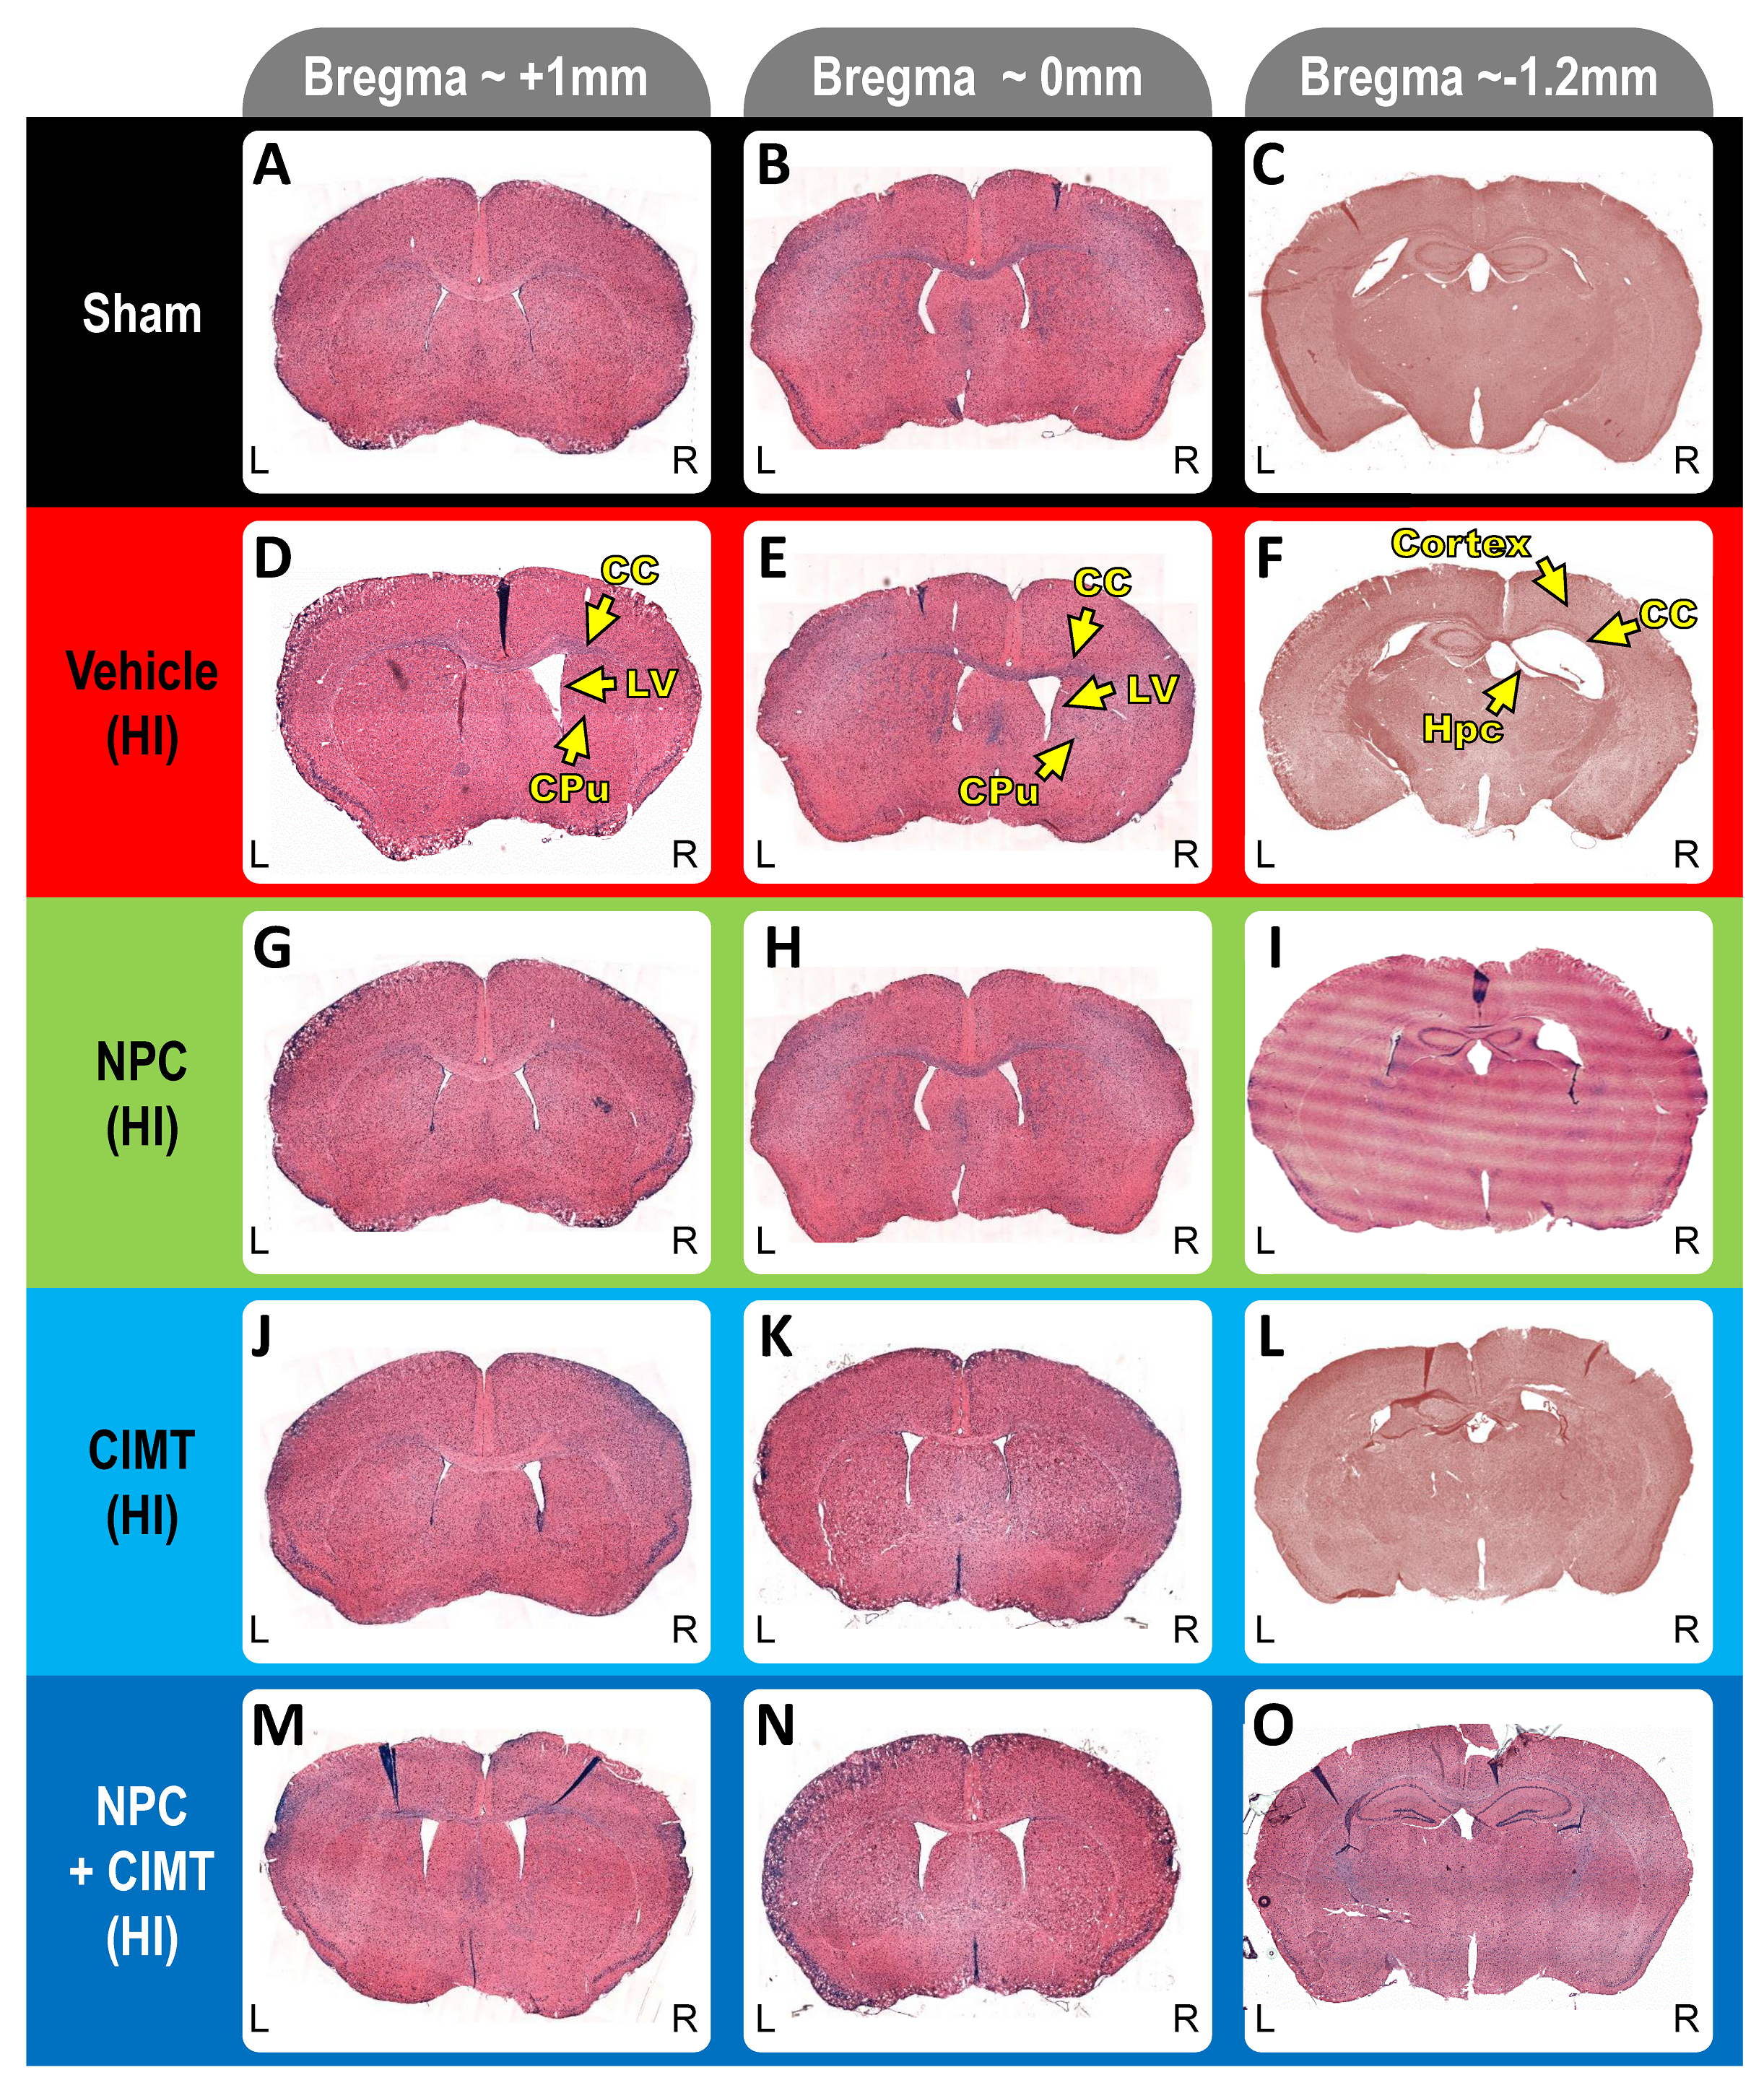

2.2. Transplanted NPCs, CIMT, and NPC + CIMT Lead to Structural Recovery

2.2.1. Neonatal HI Reduces the Overall Brain Size, but No Treatments Restore It

2.2.2. HI Injury Significantly Affects the Hippocampus, and Treatments Mitigate the Damage

2.2.3. HI Injury Affects the Cortex, and Treatment Produces Significant Recovery

2.2.4. HI Injury Significantly Affects the Corpus Callosum, and Treatment with NPCs and CIMT Leads to Recovery

2.2.5. HI Injury Notably Affects the Lateral Ventricle, and Treatment with NPCs and CIMT Leads to Significant Recovery